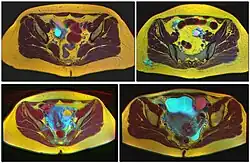

Diagnosis

Ovarian cysts are usually diagnosed by pelvic ultrasound, CT scan, or MRI, and correlated with clinical presentation and endocrinologic tests as appropriate.[15] Ultrasound is the most important imaging modality, as abnormalities seen in a CT scan sometimes prove to be normal in ultrasound.[5][8] If a different modality is needed, then MRIs are more reliable than CT scans.[5]